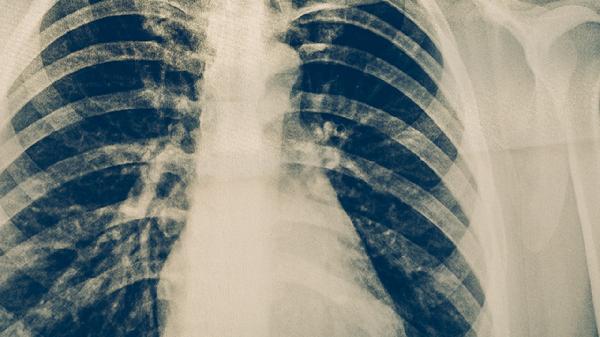

肺结核会发热不退吗 肺结核的症状表现揭晓

肺结核可能会出现发热不退的情况,肺结核的症状表现主要有咳嗽、咳痰、咯血、胸痛、发热、盗汗等。肺结核是由结核分枝杆菌感染引起的慢性传染病,主要侵犯肺部,也可能累及其他器官。